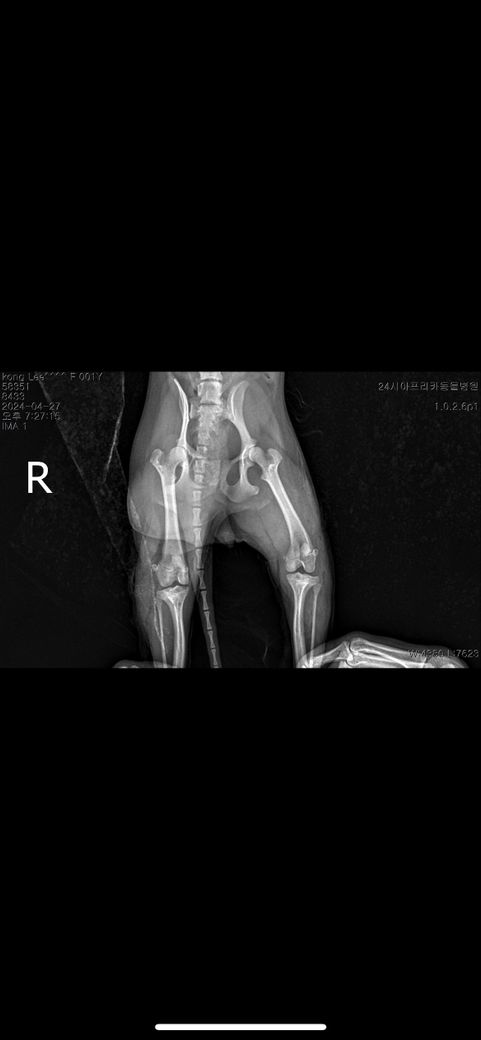

양쪽슬개골이랑 한쪽 십자인대돌아갔다해서 수술 한 상태인데 다른동물병원에서는 이 사진을 보고 십자인대를 한줄 모르더라구요 엑스레이상으로는 확인이 안되나요?십자인대 수술 된건가요?..

방사선에 나오는 device를 이용한 수술이라면 바로 알 수 있지만, 방사선에 나오지 않는 device나 autography를 이용한 수술을 하였다면 방사선 사진으로 확인할 수 없습니다.